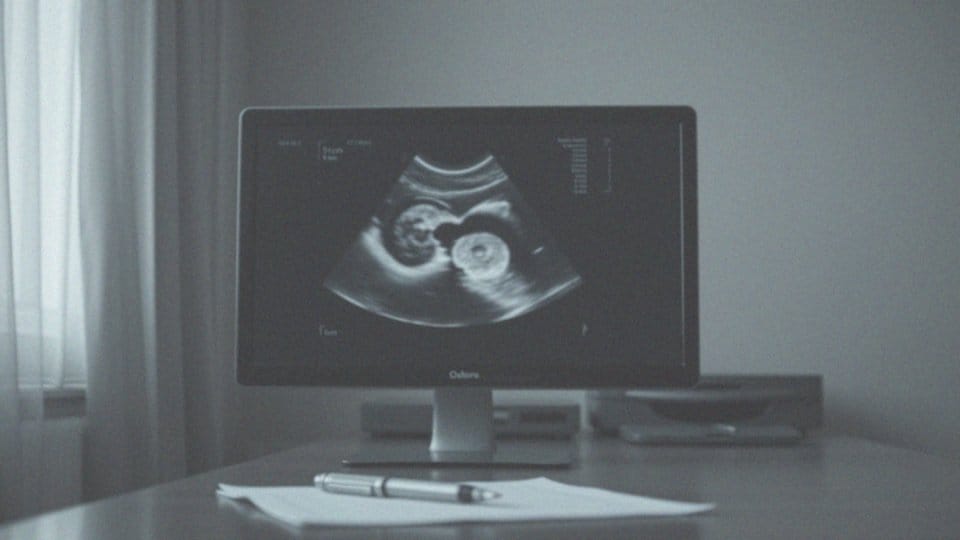

Zazwyczaj torbiele jajnikowe są wykrywane podczas badań ultrasonograficznych. Ich wygląd przypomina worek otoczony cienką błoną, a co ciekawe, nie zawsze dają jakiekolwiek objawy. Można je zidentyfikować w wyniku różnych przyczyn, takich jak:

Istotnym narzędziem w tej procedurze jest badanie ultrasonograficzne, które może być przeprowadzane:

- drogą przezpochwową,

- przezbrzuszną.

Dzięki USG możliwe jest określenie wielkości, struktury i lokalizacji torbieli, co stanowi istotny element w dalszym diagnozowaniu i planowaniu leczenia. W sytuacji, gdy charakter torbieli pozostaje niejasny, lekarz często zleca wykonanie rezonansu magnetycznego. Ta metoda pozwala na precyzyjniejszą ocenę tkank; jajników oraz wykluczenie potencjalnych zmian nowotworowych.